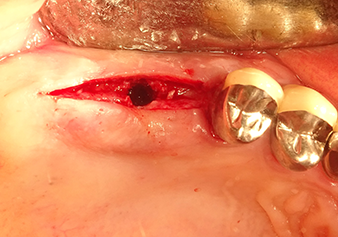

Une patiente de 49 ans, non fumeuse et sans antécédents médicaux remarquables, a été orientée vers notre cabinet de chirurgie orale pour l’extraction chirurgicale de la dent 16 préalable à la pose d’un implant. Après l’extraction, la patiente a rencontré de légers problèmes de sinusite, à la suite de quoi nous avons commencé par attendre six mois avant de prendre la mesure. À l’endroit prévu pour la pose de l’implant, l’os résiduel mesurait 3-4 mm de haut (Fig. 1 et 2).

Situation préopératoire : La crête alvéolaire a bien cicatrisé et la gencive est suffisamment large et kératinisée.

Fig.1 : Situation préopératoire : La crête alvéolaire a bien cicatrisé et la gencive est suffisamment large et kératinisée.